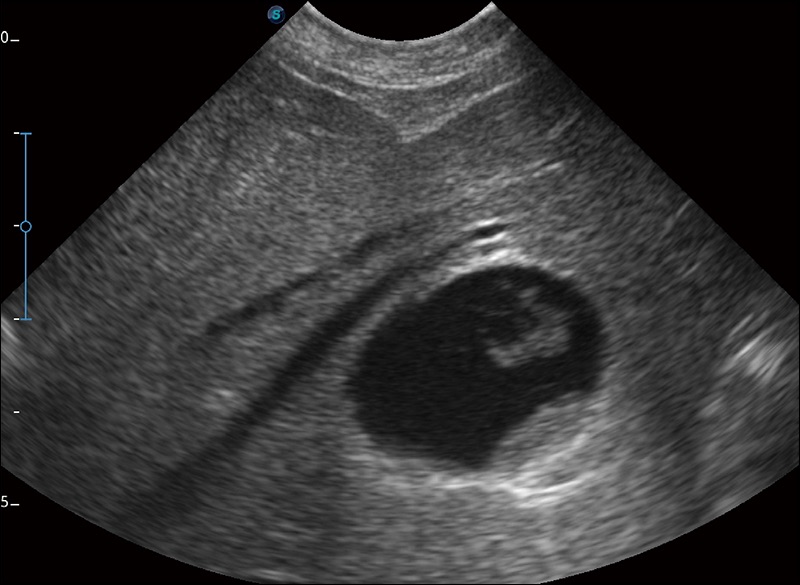

临床图